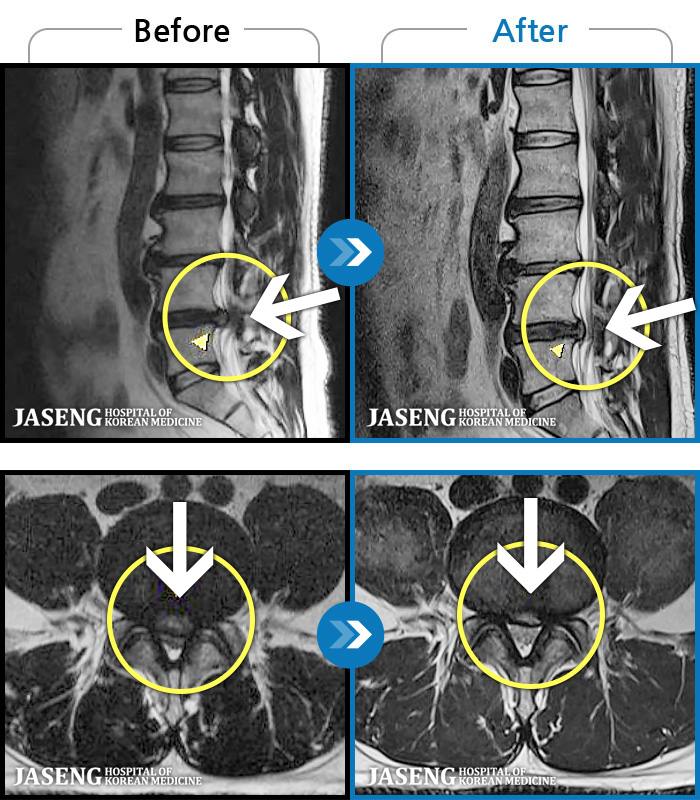

ȯںп Ǹ ǿ ԿǾ, ο ġ ۿ Ƿ ġḦ Ͻñ ٶϴ.